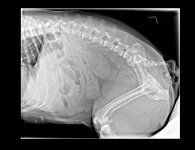

PS Attached is an excel file with the info from above, as well as a calendar grid of the same information, and blood test results from the 8th and 10th. We've requested the blood test results from the Surgeon (which would be before she got sick) and hope to have those by tomorrow. Also, I've attached the x-rays our regular vet took on the 10th.

PS Attached is an excel file with the info from above, as well as a calendar grid of the same information, and blood test results from the 8th and 10th. We've requested the blood test results from the Surgeon (which would be before she got sick) and hope to have those by tomorrow. Also, I've attached the x-rays our regular vet took on the 10th.